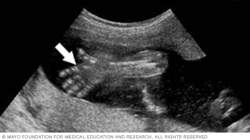

The arrow in the image below points to the site where the umbilical cord is attached to the fetus's belly, also called the abdomen. By looking at this area, the health care team can check for several conditions. They include a condition called omphalocele. It happens when contents of the abdomen come out through an opening at the bellybutton. Another condition is gastroschisis. It involves a break or split in the tissue that forms the abdominal wall.